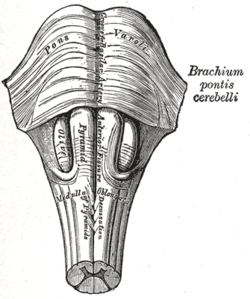

Anteroinferior view of the medulla oblongata and pons | |